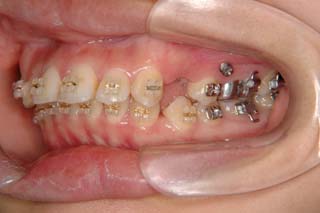

診断名:叢生を伴う上顎前突

使用した主な装置名:TPB、マルチブラケット装置、歯科矯正用アンカースクリュー

抜歯/非抜歯および抜歯部位:抜歯(上顎左右第一小臼歯)

治療期間:動的処置2年6か月、経過観察3年

かなり強い上顎前突を示します。その他の問題はなさそうですが、小臼歯抜歯だけでは上顎前突に対応しきれそうにありません。上顎大臼歯に最大限の固定が必要と考えられましたので、上顎左右の臼歯部に計2本の歯科矯正用アンカースクリューの植立を検討してみました。